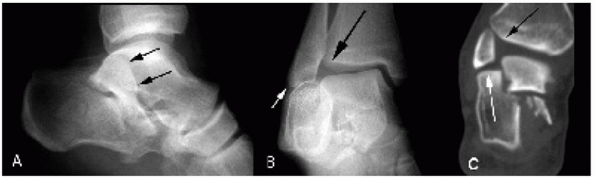

intraarticular component (Figs. 59-18 and 59-19).

FIGURE 59-19

True intra-articular tongue fracture (type IIB). Plain radiographs are unable to determine whether the fracture involves the posterior facet (A,B). Semicoronal and transverse CT scans verify intraarticular displacement (C,D). Note black arrows, indicating intra-articular fracture, and white arrows, indicating the intact lateral wall component typical of tongue fractures. |